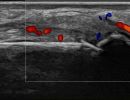

Injuries to Tendons and Ligaments

- Tendon Ruptures

- Ulnar Collateral Ligament Rupture (Skier’s Thumb)

- Ligament Injuries in Flexor Tendons (Climber’s Finger)

- Ligament Injuries in Extensor Tendons (Boxer’s Knuckle)